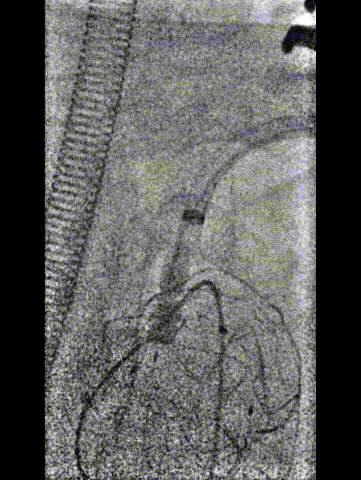

★ 左锁骨下动脉重建

从左侧肱动脉导入可调弯鞘送至左锁骨下动脉近端,同样使用asahi treasure 12导丝和支撑导管顺利通过覆膜区。依次送入4mm、6mm和8mm球囊对局部进行扩张。

将支架送入覆膜区约1cm释放支架。之后,更换更大口径的球囊送至主动脉弓内进行后扩张,使支架呈喇叭口状,以稳定两者结构,减少内漏的发生。由于左锁骨下动脉位于假性动脉瘤的破口位置,此处使用球扩覆膜支架实现了更加精准的定位,有效降低了内漏风险。

球囊回收时

带鞘进开窗口

置入VBX11-29mm支架,支架伸入

覆膜支架约1cm后释放并球扩塑形